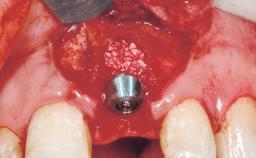

Immediate Flapless Placement of an Implant in a Maxillary Left Central Incisor Site

A 42-year-old female patient was referred to our clinic at the School of Dentistry of the University of São Paulo in November 2004, presenting a deficient restoration in the upper left central incisor. The clinical examination revealed no gingival retraction or any signs of gingival inflammation and, therefore, previous periodontal treatment was not considered. The patient presented a high lip line at full smile and a thin tissue biotype. This combination characterized a high-risk situation from an anatomic point of view, which required careful preoperative planning and cautious surgical execution.

Type of Implants One-Piece

Placement Protocol Immediate implant placement

Loading Protocol Immediate

Retention Screw-retained Screw-retained